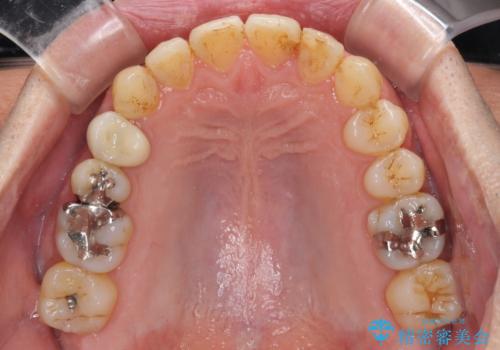

- 外に飛び出した側方の歯と、前歯のデコボコを気にして来院された患者様です。

IPR(歯と歯の間を削る)によってデコボコが解消するように設計し、インビザラインにより治療を行うこととしました。

治療途中で1年半以上通院されない時期があったため、後戻りが生じたことで治療期間が長くなってしまいました。

親知らずを抜去したことで、下顎のデコボコがきれいに解消されました。